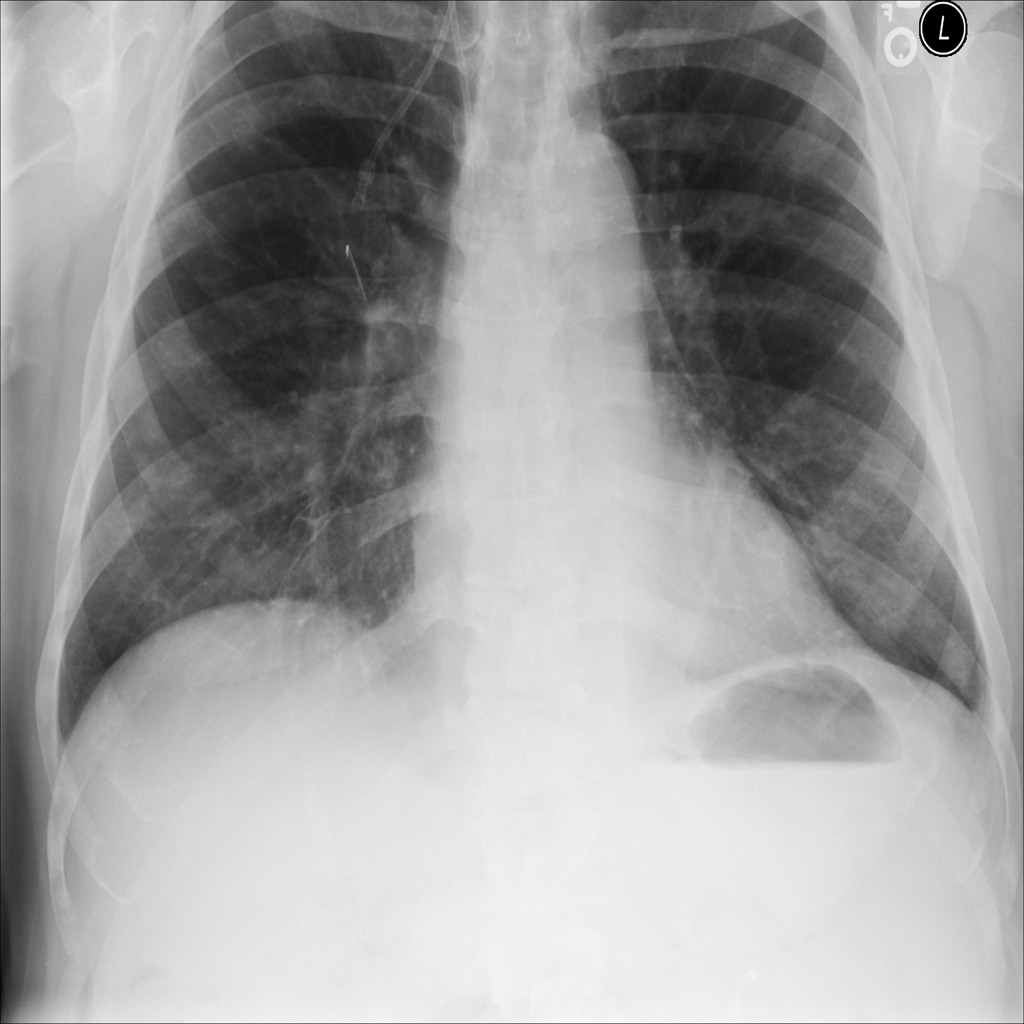

PAT-E066 · IMG-010Fibrosis

PAT-E066 · IMG-010

PA